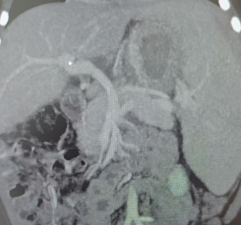

最終,多學科團隊密切合作,歷時12個小時,完成了“門靜脈左支矢狀部-供體門靜脈-頸內靜脈-腸系膜上靜脈”的精密“串聯”搭橋。術中及術后的超聲與腹部CTA檢查結果表明:重建血管保持通暢狀態,血流動力學指標表現良好,門靜脈血流阻力出現明顯降低,這意味著該患兒的門靜脈高壓已得到根本性的緩解,從而避免了消化道再次出血的風險。術后第8天,患兒康復出院。目前,患兒恢復情況良好,術后一月復查未出現嘔血、便血等癥狀,肝功能指標正常,脾臟明顯縮小,血細胞計數恢復正常。

術后門靜脈圖像